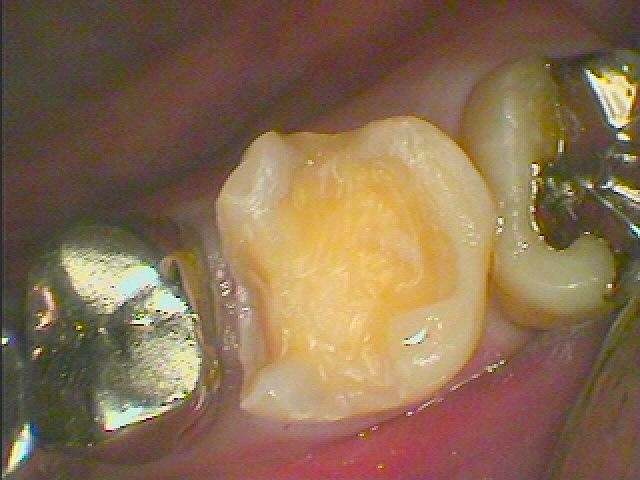

虫歯を除去していきました